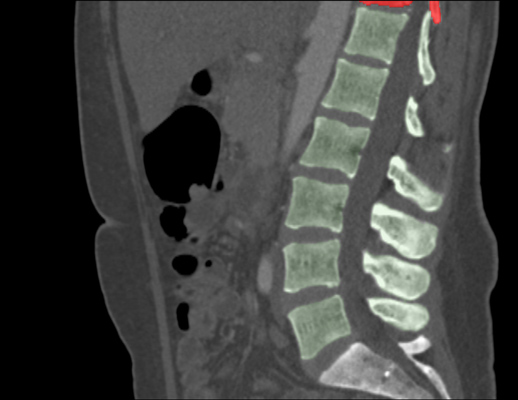

We trained and evaluated the method with five sets of CT and MR scans that visualize the spine. Reference segmentation masks for four of these datasets are publicly available, which allowed for a comparison with other publications that used the same data. Examples of images from the datasets are shown in Figure 3.

The thoracolumbar spine CT dataset consists of 15 dedicated spine CT scans that visualize all thoracic and lumbar vertebrae. It was originally used for the spine segmentation challenge held in conjunction with the Computational Spine Imaging (CSI) workshop at MICCAI 2014 (Yao et al., 2016). All subjects were young adults ( years) without vertebral fractures who were scanned with IV-contrast administration. The scans were reconstructed to in-plane resolutions of and slice thicknesses of . Semi-automatically obtained reference segmentations were provided by the challenge organizers. To allow for a comparison with the challenge results, we used the same data split with 5 scans for evaluation and the remaining 10 scans for training and development.

The xVertSeg.v1 dataset consists of 15 lumbar spine CT scans of subjects with compression fractures of various grades and types (Ibragimov et al., 2017). Manual reference segmentations are available for the lumbar vertebrae and were defined through a consensus reading of two observers. The scans were reconstructed to in-plane resolutions of and slice thicknesses of . There are currently two other publications that used the same dataset, but with different evaluation/training separation (Janssens et al., 2018; Sekuboyina et al., 2017). We therefore used the scans for evaluation and the remaining 10 scans for training.

The low-dose chest CT dataset consists of 55 scans from the National Lung Screening Trial (The National Lung Screening Trial Research Team, 2011). These scans were acquired for lung imaging and visualize in addition to the lungs a variable section of the thoracic and upper lumbar vertebrae. The scanned subjects were heavy smokers aged 50 to 74 years and therefore at increased risk for vertebral compression fractures due to their advanced age and smoking history. The scans were acquired with low radiation dose and reconstructed to in-plane resolutions of and slice thicknesses of . We created manual and semi-automatic reference segmentations for this dataset: 10 scans were used for evaluation and were therefore fully manually annotated by drawing along the contour of each vertebra in sagittal slices using an interactive live wire tool (Barrett and Mortensen, 1997). The contours were converted into segmentation masks, in which inaccuracies and other mistakes were corrected voxel-by-voxel. An additional set of 5 scans was annotated in the same way and was used to train a preliminary version of the network. This network was used to predict rough segmentations in the remaining 40 scans. These rough segmentations were manually inspected and corrected voxel-by-voxel, and were used for training of the final network. This strategy enabled us to create a large training set with substantially less manual annotation effort compared to fully manual segmentation, which is not necessarily needed for training data. Additionally, a second observer fully manually annotated two scans from the evaluation set for an estimation of the interobserver agreement. All fully manual and semi-automatic segmentations were performed in sagittal views by observers who received detailed instructions beforehand. Additionally, all segmentations were validated by an experienced radiologist.

The lumbar spine CT dataset consists of 10 scans of healthy subjects and corresponding manual reference segmentations of the lumbar vertebrae (Ibragimov et al., 2014; Korez et al., 2015). The scans were reconstructed to in-plane resolutions of and slice thicknesses of . Because this dataset is the smallest of the datasets that we included, it was used for an external evaluation of our supervised approach. Scans from this dataset were therefore only used for evaluation and were not part of the training set.

The lumbar spine MR dataset consists of 23 T2-weighted turbo spine echo MR images acquired at 1.5T in sagittal orientation (Chu et al., 2015). The scans have a resolution of . Manual reference segmentations are available for 7 vertebrae (T11-L5) in all scans. These reference segmentations contain only the vertebral bodies, not the entire vertebrae.